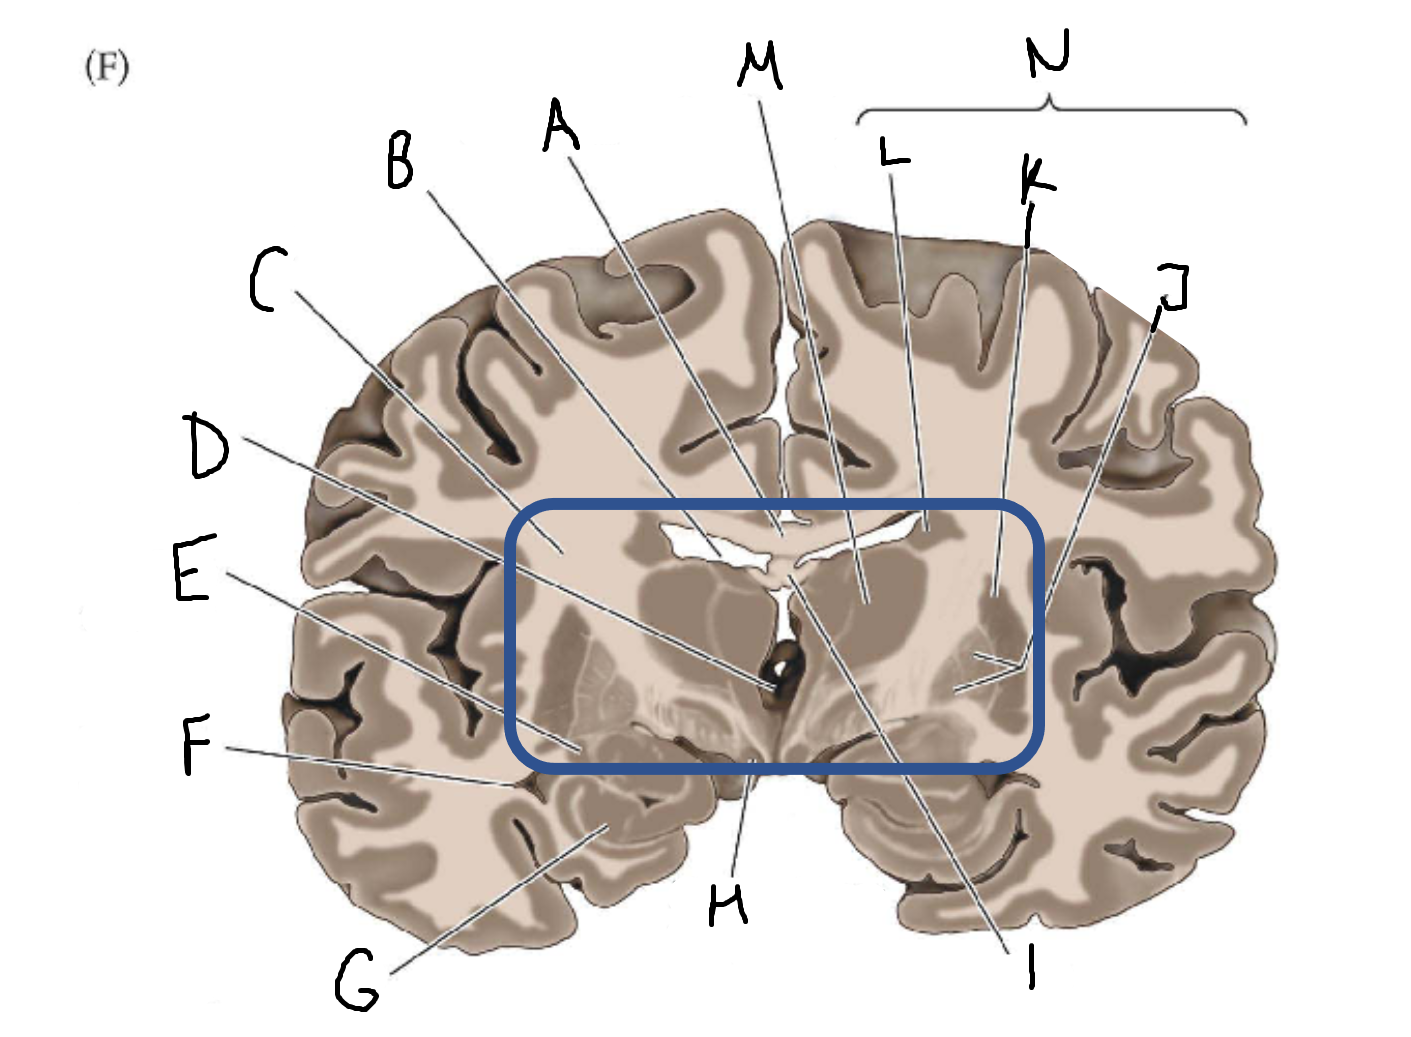

A

corpus callosum

B

lateral ventricle

C

internal capsule

D

third ventricle

E

tail of caudate nucleus

F

lateral ventricle

G

hippocampus

H

mammillary body

I

fornix

J

globus pallidus

K

putamen

L

caudate

M

thalamus

N

basal ganglia